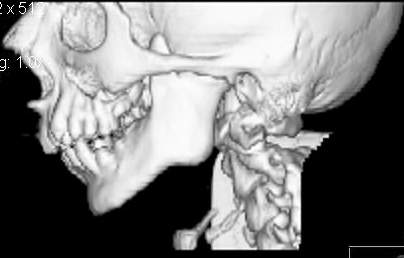

Пациент В., 13 лет. Диагноз: Костный анкилоз левого височно-нижнечелюстного сустава (ВНЧС), левосторонняя микрогения. Болеет с 2-х летнего возраста. Возможная причина развития анкилоза – воспалительный процесс (в первые 1,5 года жизни часто болел простудными заболеваниями, травму родители отрицают). В 3 и 5 лет проводилась редрессация – безуспешно.Прилагаются: ортопантомограмма, кадры СКТ с 3Д реконструкцией. Вопросы: определение тактики лечения – вид и сроки реконструктивно-пластической операции (этапов операции), а именно – неоартропластики и устранения микрогении, медикаментозная терапия в до- и послеоперационный период, ортодонтическое лечение.